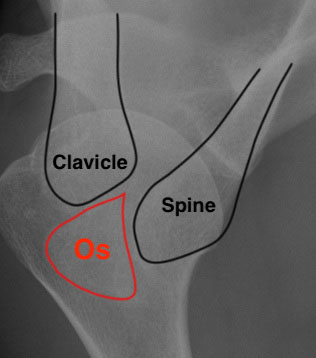

X-ray

Best seen on axillary lateral

Factors favoring diagnosis of os acromiale over fracture

- bilateral occurrence (xray other side)

- rounded borders with uniform space

Axillary lateral showing meso-acromion Scapula lateral xray showing os acromiale